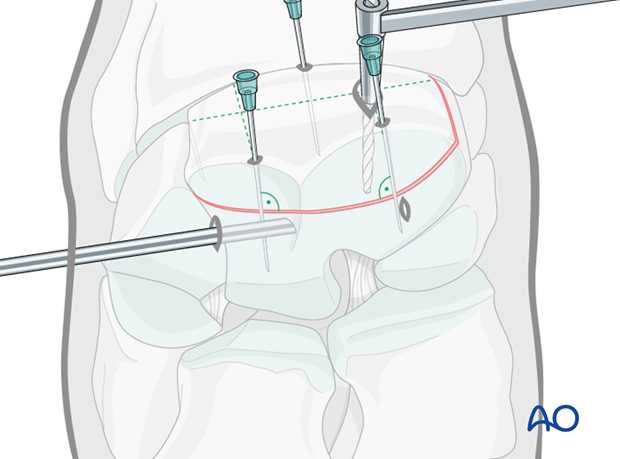

The proximal medial and lateral margins of the fracture are defined by arthroscopically guided percutaneous insertion of 18 gauge hypodermic needles.

It is important that these needles are placed perpendicular to the dorsal surface of the carpus in order to accurately delineate the fracture width.

Two 18 gauge spinal needles are then placed over the central portion of the radial and intermediate facets of the third carpal bone. These two needles are close and parallel to the proximal articular surface and directed approximately perpendicular to the fracture line. These needles are critical guides for implant placement. Once the spinal needles have been placed, the lateral and medial hypodermic needles are removed.

Based on the radiographs two stab incisions are placed over the dorsal aspect of the radial and the intermediate facets respectively. Their positioning is based on radiographs of spinal needle placement.

Two 4.5 mm glide holes are drilled through fragment until they enter the fracture line (the distance is predetermined by measurement by the radiographs).

The drill depths can be verified using an intraoperative radiograph.

The 3.2 mm drill guide is inserted into one glide hole and the 3.2 mm thread hole is drilled through the remaining third carpal bone. The hole is drilled through the entire parent third carpal bone so that maximal screw length can be used.